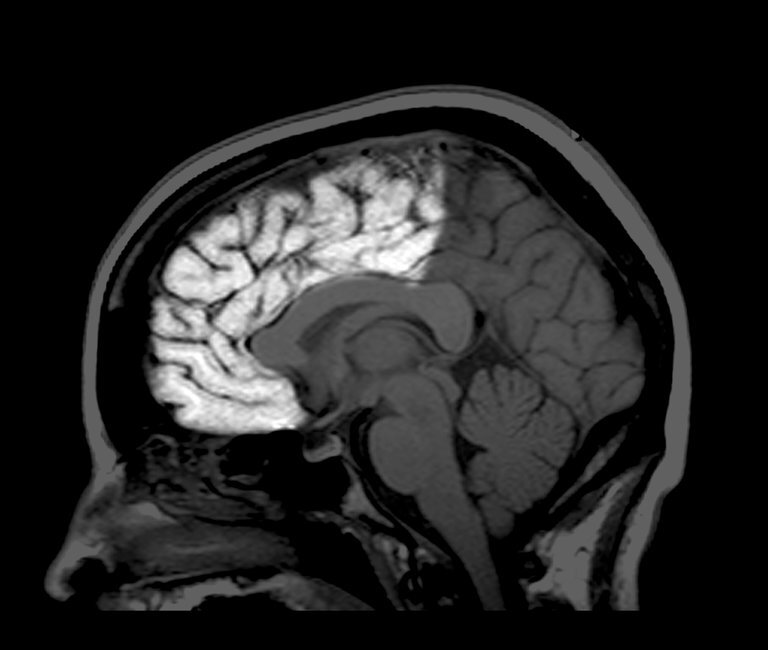

Aunque te consideres adulto, puede que tu cerebro no lo sea

A pesar de que los 18 años sean el límite de "la edad adulta", poseer un cerebro adulto no va ligado a la edad biológica, y la maduración cerebral tampoco.

Esencialmente, el cerebro humano alcanza su volumen total alrededor de los 10 años de edad. Sin embargo, nuestras neuronas siguen desarrollándose y cambiando durante años, y las conexiones entre ellas también. Posteriormente, esta formación va desacelerándose poco a poco, un signo inequívoco de que el cerebro adulto está madurando. Pero este proceso ocurre a diferentes velocidades en cada parte del cerebro.

Por ejemplo, en el lóbulo occipital (zona posterior del cerebro, en la nuca), madura alrededor de los 20 años de edad; por su parte, el lóbulo frontal (en la zona anterior del cerebro), sigue creando nuevos enlaces hasta los 30 años e incluso más allá.

Si nuestro cerebro cambia a nivel anatómico, su actividad también cambia. Por ejemplo en los niños, las regiones cerebrales vecinas suelen trabajar a la vez. Pero en la edad adulta, son las regiones más separadas las que acaban sincronizándose. Según los neurocientíficos, esta armonía “a larga distancia” permitiría que el cerebro adulto trabaje de forma más eficiente y sea capaz de procesar más información.